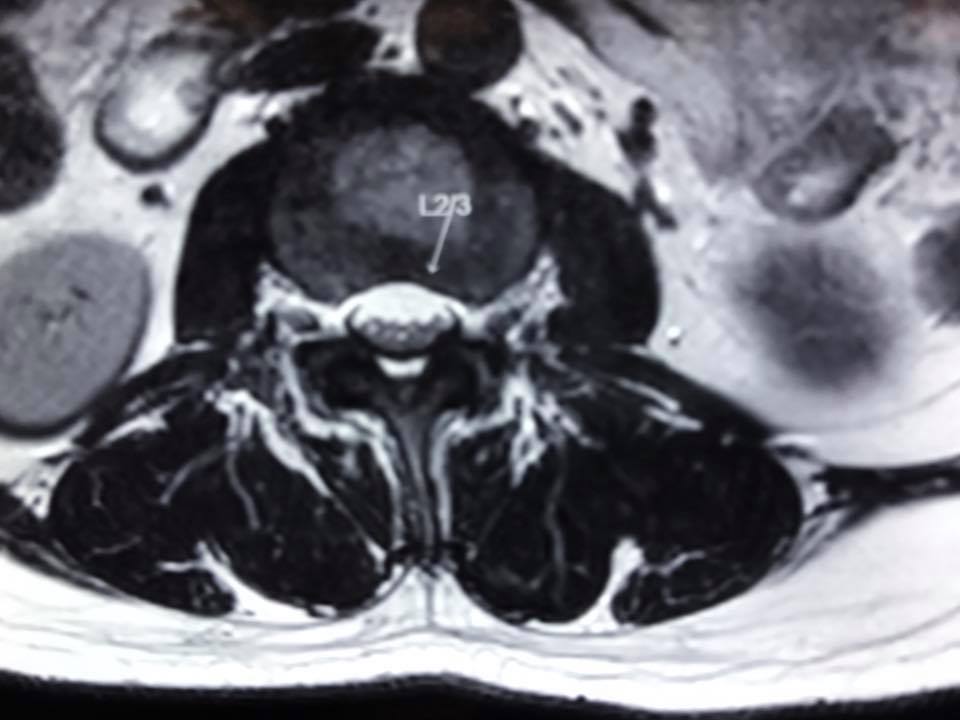

半急症類別,及早手術減壓...以防止神經永久受損而不能服原.

1. 引致椎間盤突出

2. 和因退化及腰椎不穏定…而增生肥大的韌帶

兩者一起擠壓著馬尾神經線.